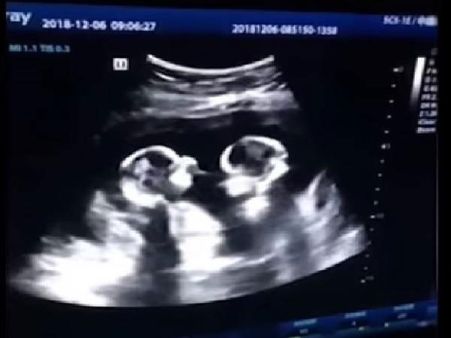

અલ્ટ્રાસાઉન્ડમાં દેખાઈ ગર્ભમાં જોડિયા બાળકોની લડાઈ, વિડીયો વાયરલ

કોઈપણ માતાપિતાને ગર્ભમાં જોડિયા બાળકોના સમાચાર સાંભળવામાં ખુશી થશે પરંતુ તમે ત્યારે કેવી પ્રતિક્રિયા આપશો જયારે તમને ખબર પડશે કે આ દુનિયામાં આવતા પહેલા, તે બાળકોએ ગર્ભાશયમાં જ લડવાની શરૂઆત કરી છે? સાંભળવામાં તે ખૂબ વિચિત્ર લાગશે. અહીં અમે એક વિડિઓ શેર કરી રહ્યા છીએ જેમાં જુડવા શિશુ સ્કેન દરમિયાન એકબીજા સાથે લડાઈ કરતા દેખાય છે. આ લેખ દ્વારા તમે પણ જુઓ આ વિડીયો.

સૂત્રોના જણાવ્યા અનુસાર, આ વિડીયો ગયા વર્ષનો છે, ચીનમાં એક વ્યક્તિએ તેની ગર્ભવતી પત્નીના અલ્ટ્રાસાઉન્ડ દરમિયાન રેકોર્ડ કર્યો હતો. તેના ગર્ભાશયમાં જુડવા છોકરીઓ હતી અને તે અલ્ટ્રાસાઉન્ડના સમયે ચાર મહિના પૂર્ણ કરી ચુકી હતી.

અલ્ટ્રાસાઉન્ડ સ્કેન વિડીયોમાં, બંને ભ્રુણ એક બીજાને લાત અને હાથ મારતા જોવા મળ્યા. પિતાએ આ વિડીયો સોશિયલ મીડિયા પર શેર કર્યો અને તે ખુબ વાયરલ થઇ ગયો.